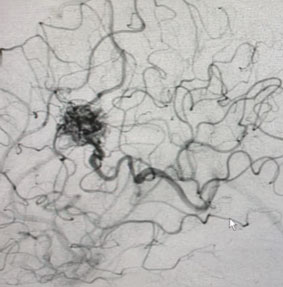

Angiogram (Figure 3 and 4) confirmed the presence of a deep left frontal AVM without any associated aneurysms.

Fig. 3